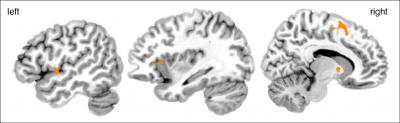

If a melody was judged as being improvised, regardless of whether this was in fact the case, stronger activity was found in a network which is known to be involved in the covert simulation of actions. This network comprised the frontal operculum, the pre-supplementary area and the anterior insula.

"We know today that during perception of actions, similar brain areas are active as during the execution of the same action", explains Annerose Engel. "This supports the evaluation of other people's behaviour in order to form expectations and predict future behaviour." If a melody is perceived as being more difficult to predict, for example, because of fluctuations in loudness and timing, stronger activity is most likely to be elicited in this specialised network.